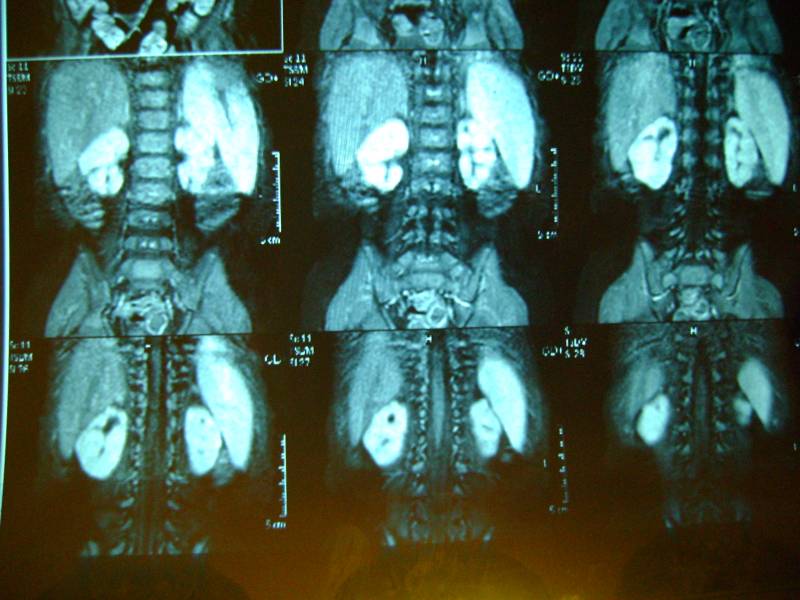

еще